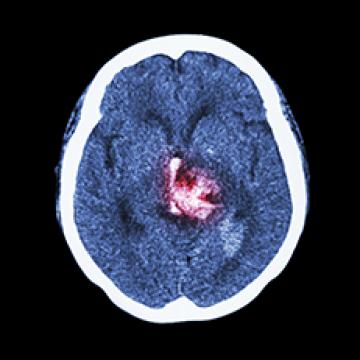

In order to understand cerebral palsy, it’s important to understand how our brain and body works and connects. Cerebral Palsy is caused by an injury to the developing brain occurring before, during or shortly after birth. This early brain injury often means the brain is not easily able to send clear messages to the body (such as to the muscles). As a result, posture and movement control, and sometimes other aspects of function, may be ‘impaired’. The more you understand, the more you’ll be able to help support your child, encourage skill development and improve outcomes. As you explore CP Resource articles that are about understanding how your brain & body works will be color coded teal.

Understanding Brain Injury in Cerebral Palsy -